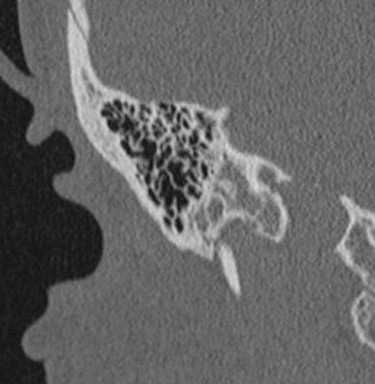

Рис 1. Активная форма отосклероза: плотность очагов +300 - +800 ед. Н.

При смешанных формах, выявленных по КТ височных костей, помимо фенестральной локализации очагов отоспонгиоза или отосклероза, определяются участки пониженной плотности капсулы лабиринта, окружающие улитку, распространяющиеся на область круглого окна, иногда до дна внутреннего слухового прохода (рис. 2). При смешанной форме распространения очагов отоспонгиоза или отосклероза, выявленных по КТ височных костей, по данным ТПА определяется смешанная форма тугоухости (1-2 ст.).

Рис. 2. Смешанная форма отосклероза (плотность очагов отоспонгиоза +300- +800 ед. Н).

При кохлеарном отосклерозе, в начальной его стадии в костной капсуле лабиринта, окружающей улитку, выявляются участки пониженной плотности +1500- +1100 ед. H. При умеренно выраженной активной стадии - в костной капсуле лабиринта, вокруг базального и апикального завитков улитки определяются хорошо видимые на томограммах участки пониженной плотности +1000- +600 ед. H, часто распространяющиеся на область круглого окна и могут достигать дна внутреннего слухового прохода и горизонтальных полукружных каналов (рис. 3).

Рис. 3. Кохлеарная форма отосклерза (плотоность очагов + 600 - +800 ед. Н).

На стадии далеко зашедшего кохлеарного отосклероза выявляется деминерализация костной капсулы ушного лабиринта на уровне базального и апикального витков улитки. Также изменения могут достигать преддверия и полукружных каналов. Плотность на этой стадии колеблется от +300 до +1200 ед. H. На этой стадии развития отосклероза могут определяться явления костной облитерации структур лабиринта. Наиболее часто явления облитерации по данным КТ височных костей выявляются в базальном завитке улитке и горизонтальном полукружном канале (табл. 1).